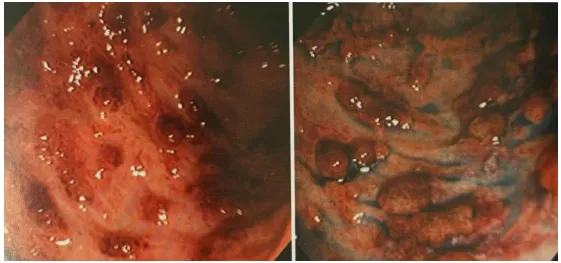

图2 活动期内镜及病理组织学所见(中型)

左上、右上、左下:内镜所见,被称为珊瑚礁状黏膜,溃疡性结肠炎的典型图像,血管透见消失,弥漫性溃疡,残存黏膜所致凹凸不平,易出血,脓液附着

右下:隐窝脓肿